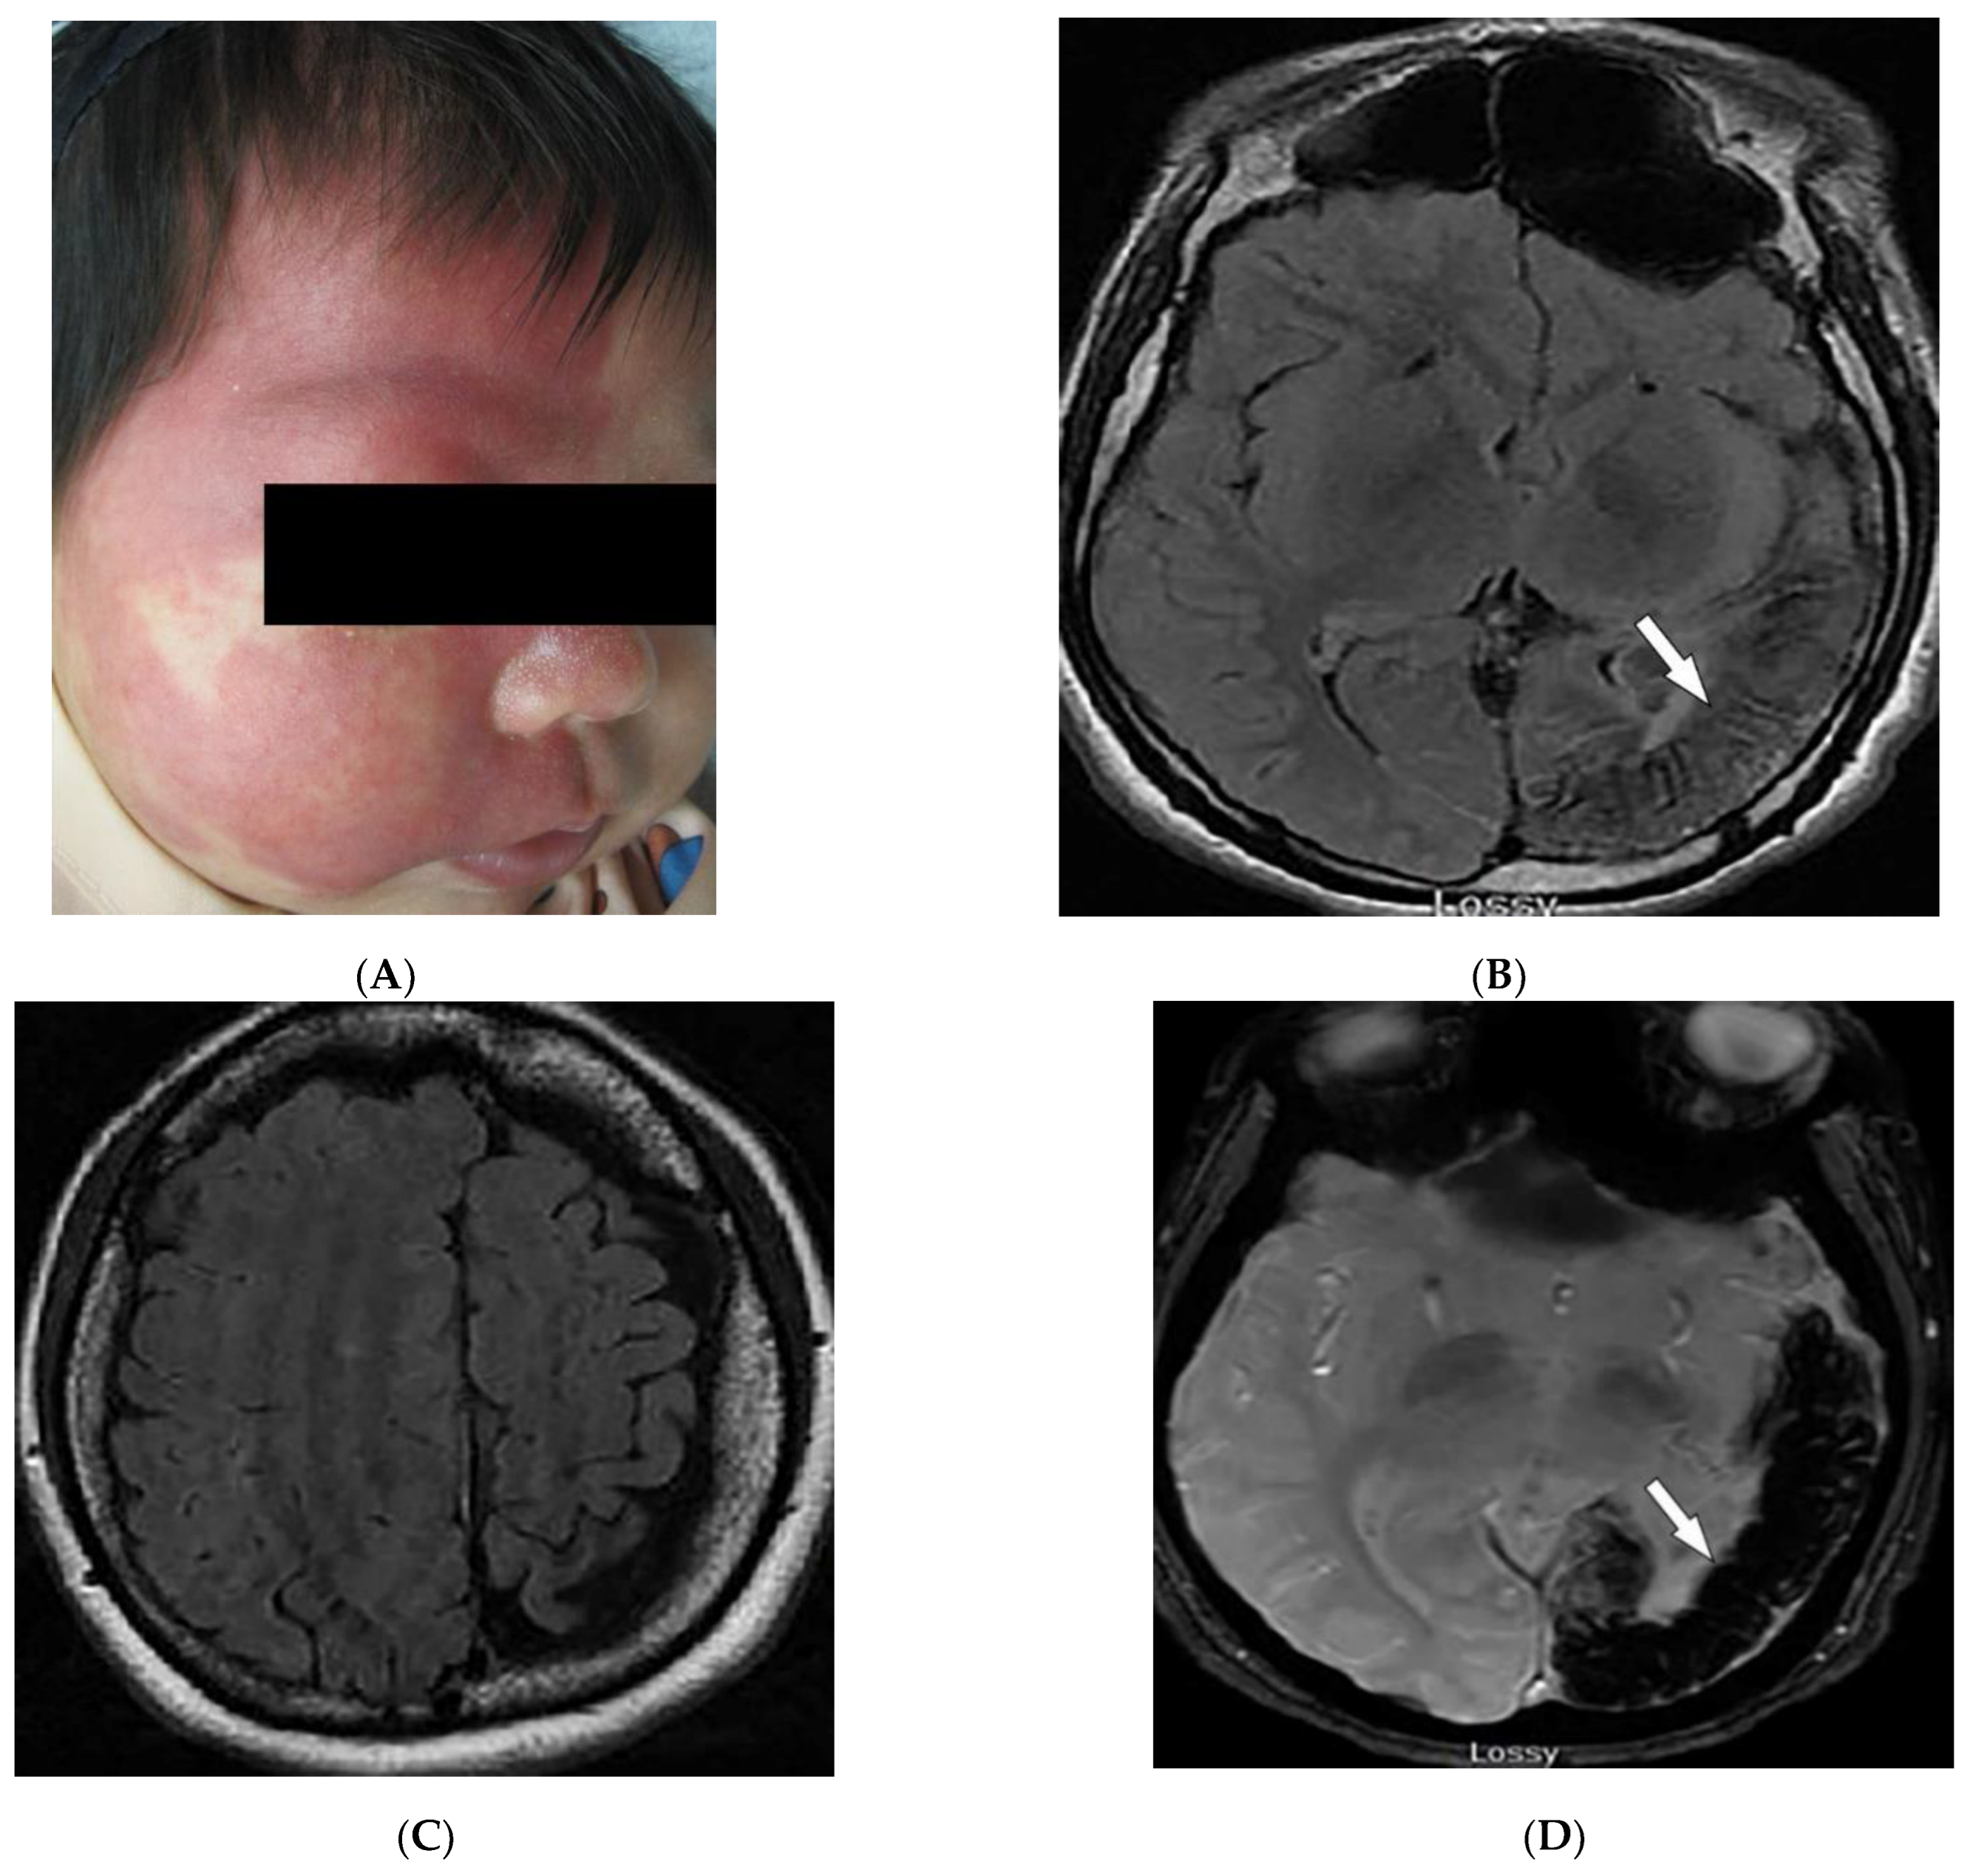

3.3. Sturge–Weber Syndrome

3.4. PHACES Syndrome

| PHACES syndrome | Craniofacial hemangiomas Posterior fossa malformations Cerebrovascular anomalies Eye anomalies | Ipsilateral cerebellar hemisphere dysplasia Major cerebral vessels dysplasia |